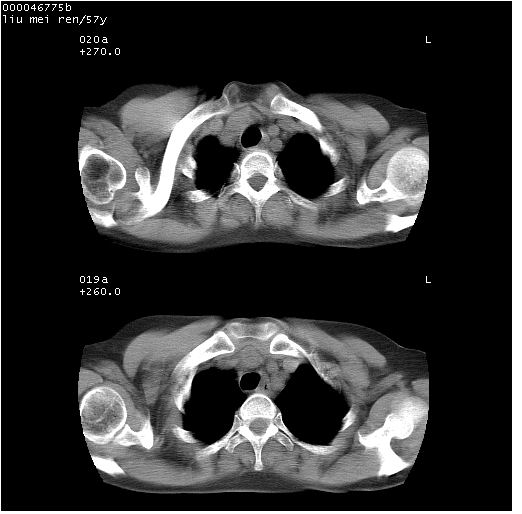

患者 女,57岁。因车祸受伤,其家属要求行“全身ct检查”。平素健康。

胸部ct轴位平扫(层厚10mm,螺距1.5,重建间隔10mm),图像如下:

左位上腔静脉,先天变异。

左位上腔静脉,先天变异。与双侧上腔静脉区别。